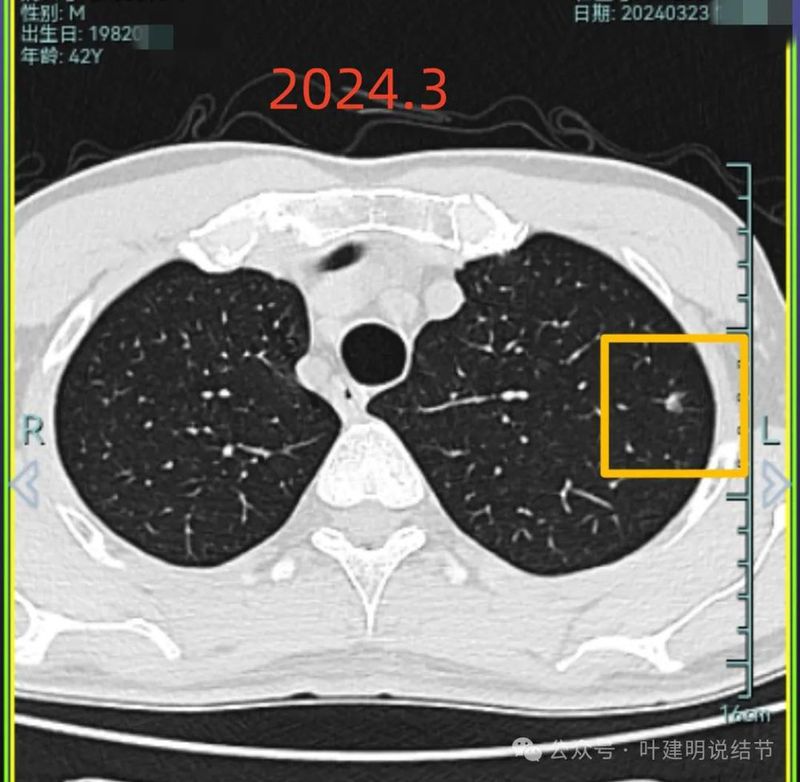

2024年3月时左上病灶感觉密度更高了点。

右中叶与左上叶的都考虑是肿瘤范畴的,对比其实2019年时就有,红色的是右中叶的,没有显著进展变化,考虑原位癌可能性较大;桔色的是左上叶的,略有进展,考虑慢性炎伴肺泡上皮不典型增生或肺泡上皮增生可能性大,近期风险仍不算大,我觉得可以先常规年度复查随访,若有进展再考虑干预处理,可楔形切除的。意见供参考!